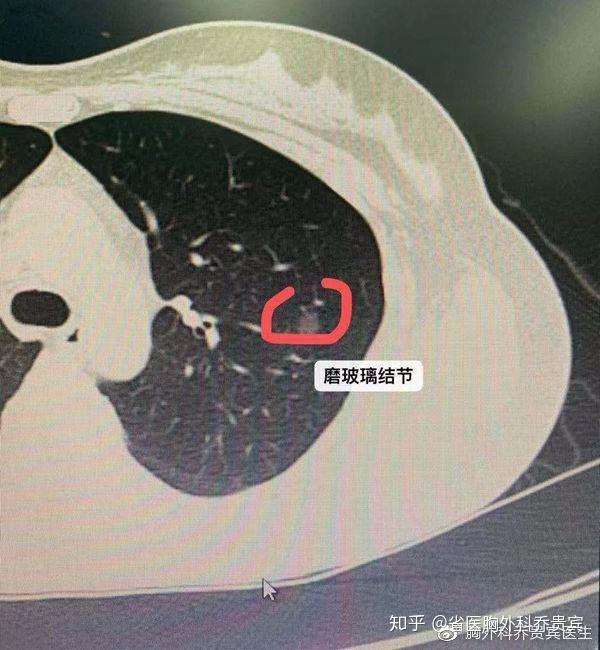

分叶征 / "分叶征"是指结节边缘不光滑,呈分叶状.